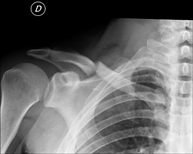

- Limb X-ray

This technique uses X-ray imaging to examine the limbs, especially the bones. Indicated for: trauma, joint infections.

Técnica mediante la cual, utilizando rayos X, se obtienen imágenes del esternón para su estudio. - RX Clavículas

Técnica mediante la cual, utilizando rayos X, se obtienen imágenes de las clavículas para su estudio. - RX Parilla costal